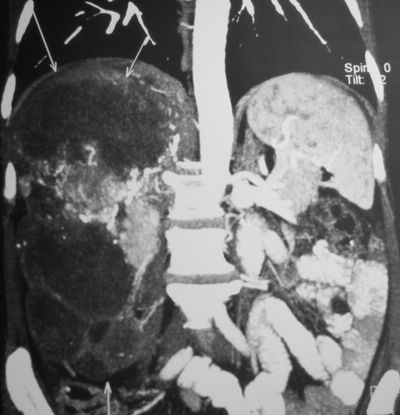

КТ органов брюшнйо полости